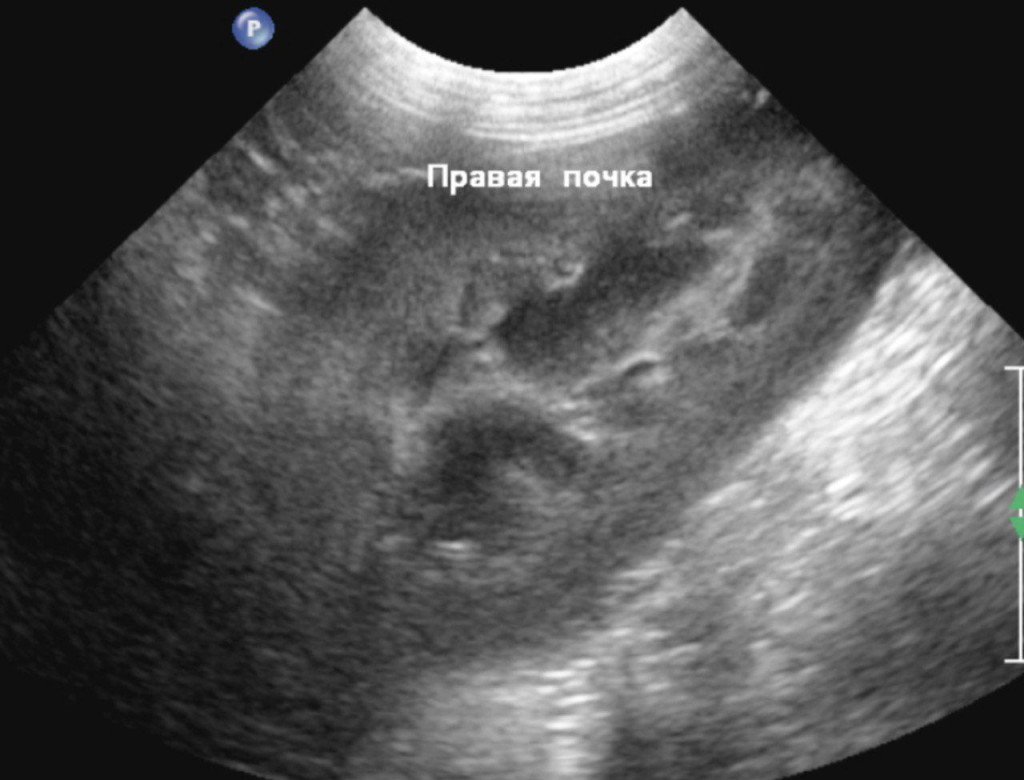

При повторном ультразвуковом исследовании почек (рис. 5, 6) не наблюдалось значительных изменений за исключением слабовыраженной пиелоэктазии на фоне инфузионной терапии. Паренхима печени также не демонстрировала динамики по сравнению с предыдущим ультразвуковым исследованием, однако желчный пузырь имел некоторые изменения: он был овальной формы с размерами 38,8×20,2 мм и утолщенной стенкой до 1,6 мм. Содержимое просвета пузыря было смешанной эхогенности. Конкременты не визуализировались. На основании этих данных у нас возникло предположение о формировании мукоцеле желчного пузыря, хотя также нельзя было исключать холецистит.